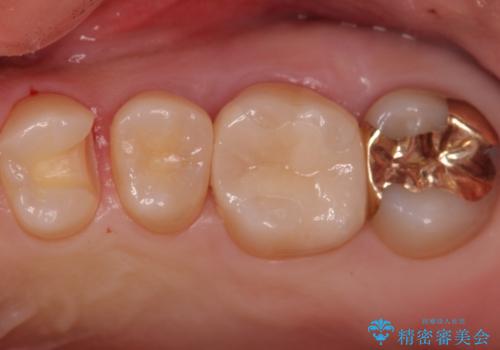

歯と歯の間の虫歯 インレーでの治療(セラミック・ゴールド)

- 銀歯のやり替えと虫歯の治療をご希望で来院された患者様です。

一番奥の歯は外から見えにくい部分であるためゴールドインレーで修復します。

その他はセラミックインレーで修復します。

- 左上46:セラミックインレー/77,000円×2 左上7:ゴールドインレー/77,000円×1費用は治療当時の料金となります

噛みしめの強い方や、外から見えないような部分では、割れる心配のないゴールドインレーをおすすめします。